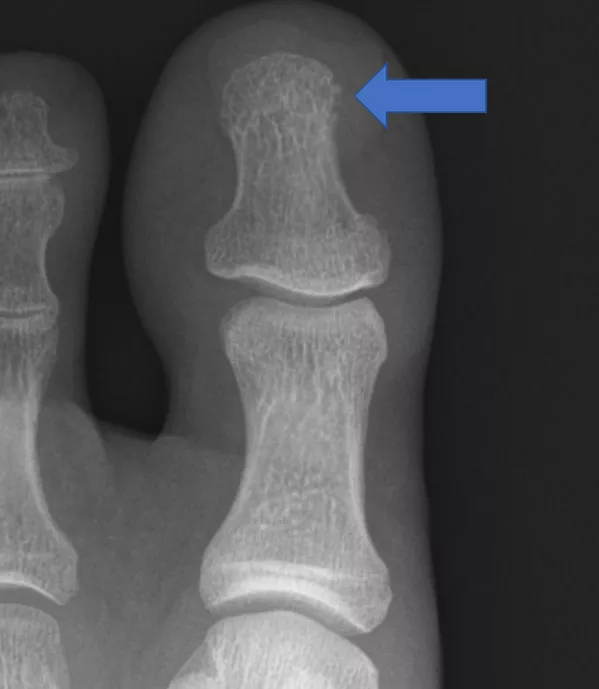

図2.足趾の単純X線

末節骨末端骨吸収像

と骨新生像